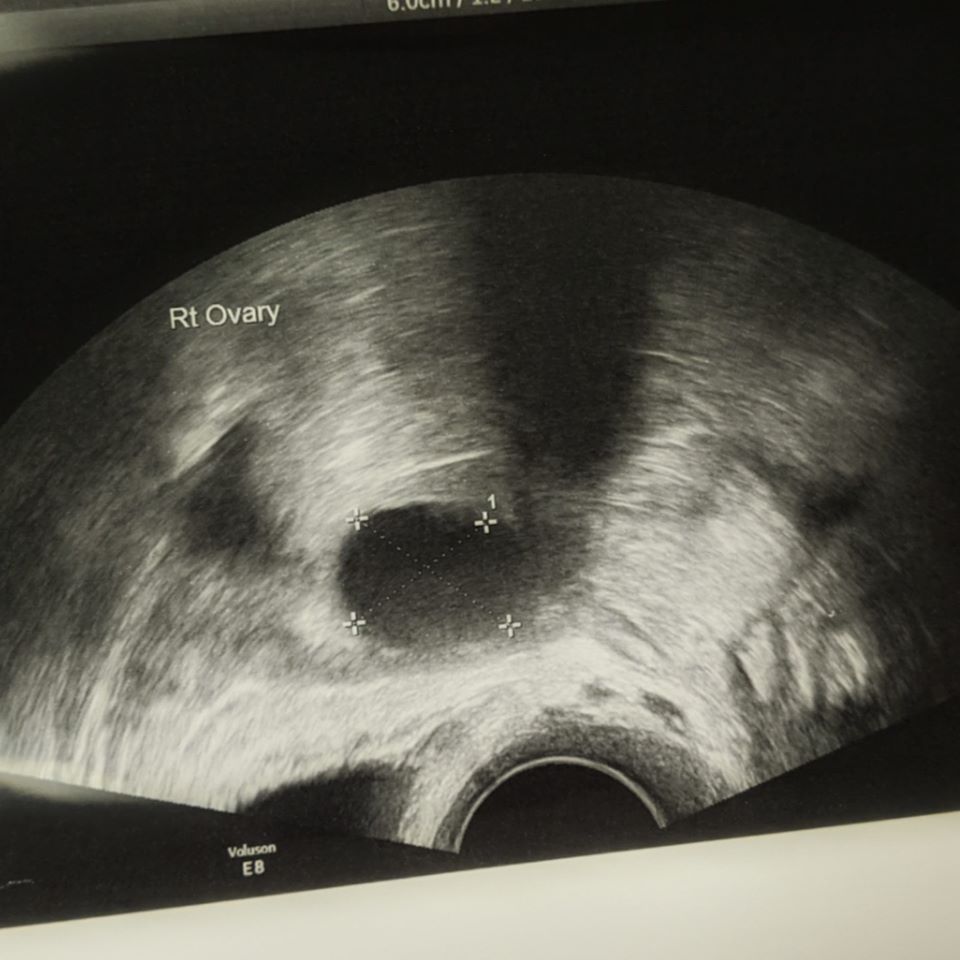

One of the follicles on the right ovary had grown to 17mm, and she told me about the “three lines” on my uterus which is good for womb lining and implantation – so I was happy that my body was doing what it was doing I was booked in for a baseline scan and to check ovulation 5 days later. Normally follicles are to be 18mm+ for ovulation – so I was happy I was almost there!